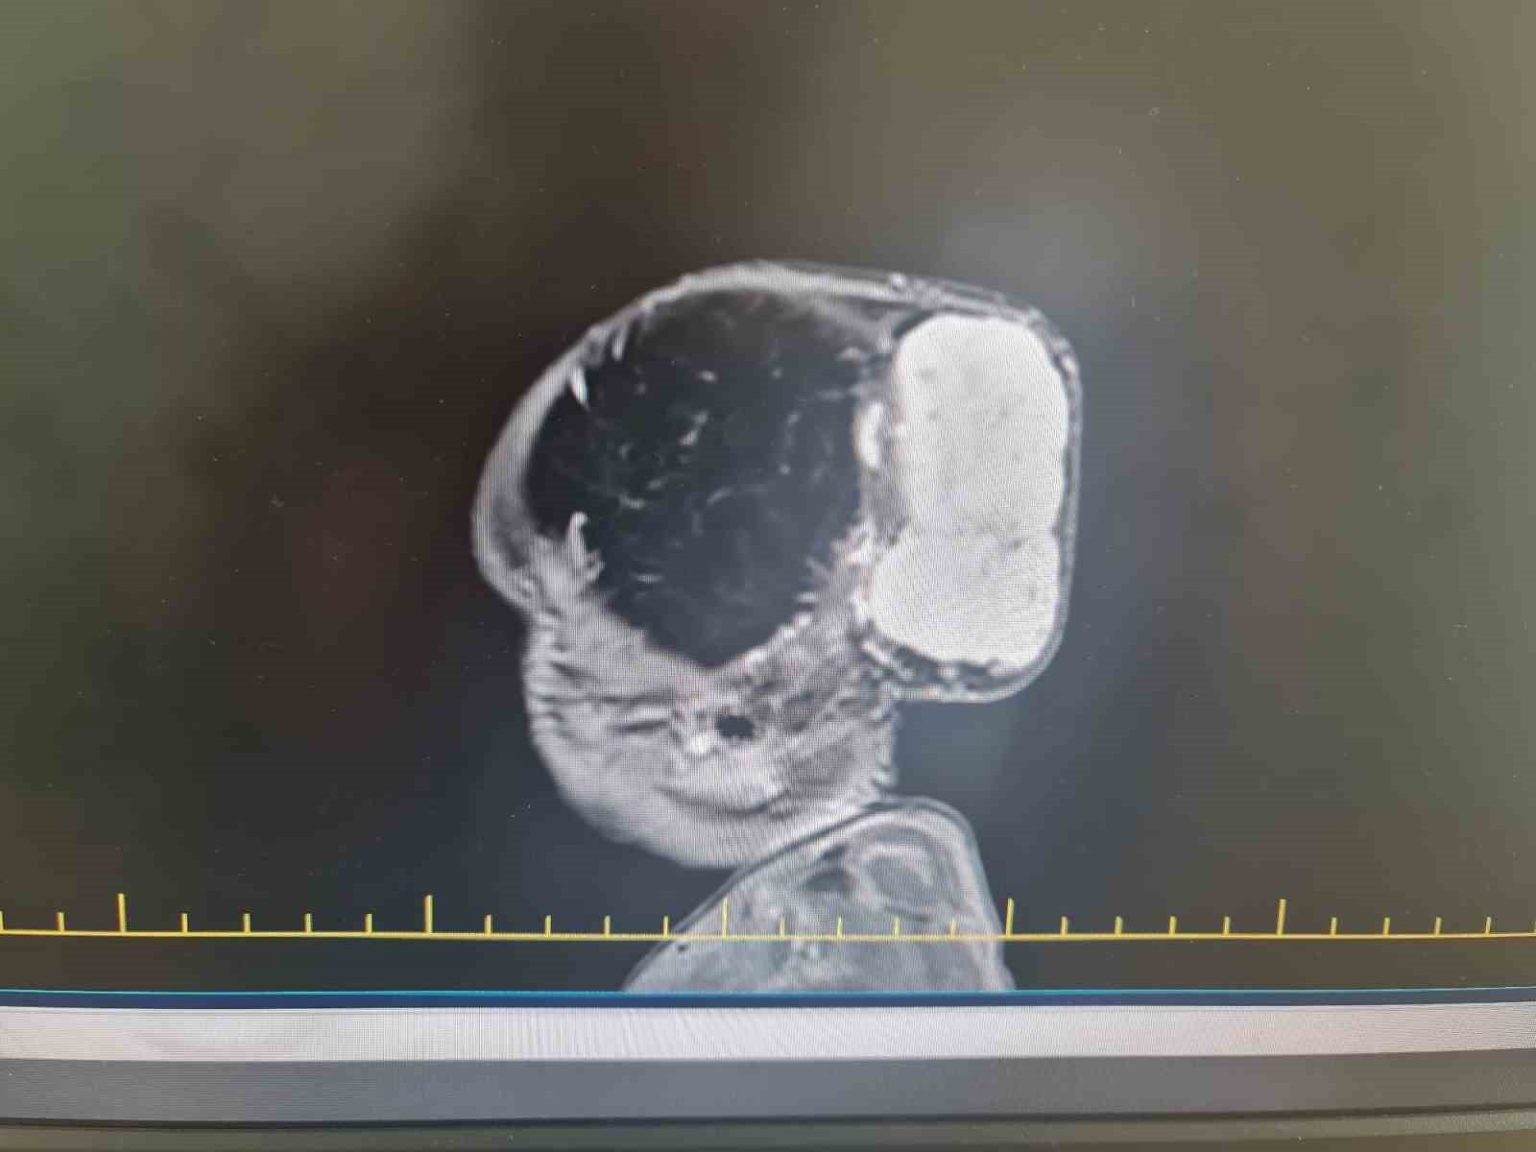

Gaziantep’te Yalçın Enes ve Tuğba Yalçın çiftinin 1,5 yaşındaki çocukları Talha, Gaziantep Şehir Hastanesinde kafasında büyük bir kitle ile dünyaya geldi. Aynı hastanede yapılan tetkiklerde minik Talha’nın kafatasında 7 x 6,5 x 4 santimetre boyutlarında, dünyada nadir görülen vakalar arasında yer alan bir tümör tespit edildi.

Bu tarz tümörlerin nadir olarak görüldüğünü aktaran Op. Dr. Ali Yayla, bebeğin taburcu olmasında herhangi bir sorun olmadığını söyleyerek, “Tümörün boyutları yaklaşık 7 x 6,5 x 4 santimetre çaplarındaydı. Bu büyüklükte bir tümör dünyada nadir bir şekilde bu yaş grubunda görülebiliyor. Bu operasyonu başarılı bir şekilde Gaziantep Şehir Hastanesi’nde uygulamak da bizim için büyük bir gurur oldu. Taburcu olmasında herhangi bir sorun yok bugün dördüncü günü. Ama biraz daha bekleyip güvende olmasını istiyoruz. Dolayısıyla dördüncü gün tamamladık, beşinci gün taburcu olabilir” ifadelerini kullandı.